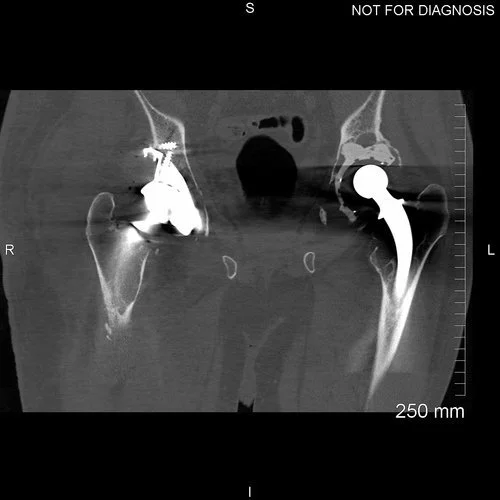

Pre-Op Radiograph shows loosening of both acetabular components. From the radiograph it is difficult to gauge the size of the acetabular defect

Pre-operative radiographs of the knees were to identify if degenerative joint disease in the knees was causing the reported knee pain. Some degenerative disease is present, however the source of the pain is the loosened acetabular component in the right hip

Loose right acetabulum of a metal-on-plastic THR with some subluxation. Loose left acetabulum.